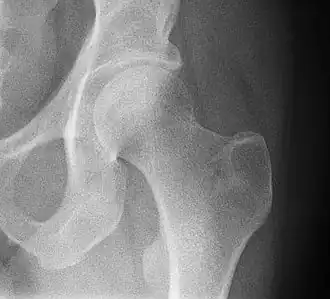

![]() Рентгенограмма тазобедренного сустава. | |

Та́зобе́дренный суста́в (лат. articulatio coxae) — чашеобразный, многоосный сустав, образованный полулунной поверхностью вертлужной впадины тазовой кости и суставной поверхностью головки бедренной кости. Вертлужная губа, сращённая с краем вертлужной впадины, углубляет последнюю.